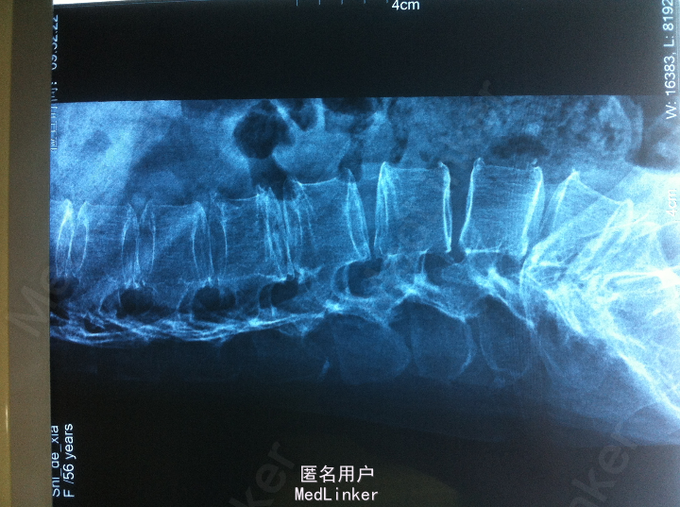

查体:腰部叩痛,腰部活动受限,左侧小腿外侧、足背感觉减退,左侧踝背伸、踇背伸、跖屈肌肌力4级,右侧踝背伸、踇背伸、跖屈肌肌力4-5级,双侧膝腱反射+,跟腱反射+,双侧巴氏征阴性。辅助检查: X-ray:腰椎退行性变节段性不稳。CT:腰椎间盘突出,腰3/4,4/5,腰5/骶1, MR:腰椎间盘突出,腰3/4,4/5,腰5、骶1椎间盘突出。